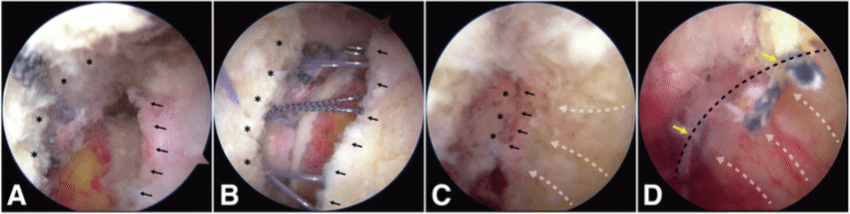

国际首创关节镜下软骨钉植入治疗髋臼软骨剥脱损伤,目前髋组已完成数十例髋关节镜下软骨剥脱修复术,在手术指征的选择,手术技术,围手术期管理等方面有较为先进的经验,处于国内领先,国际一流地位。